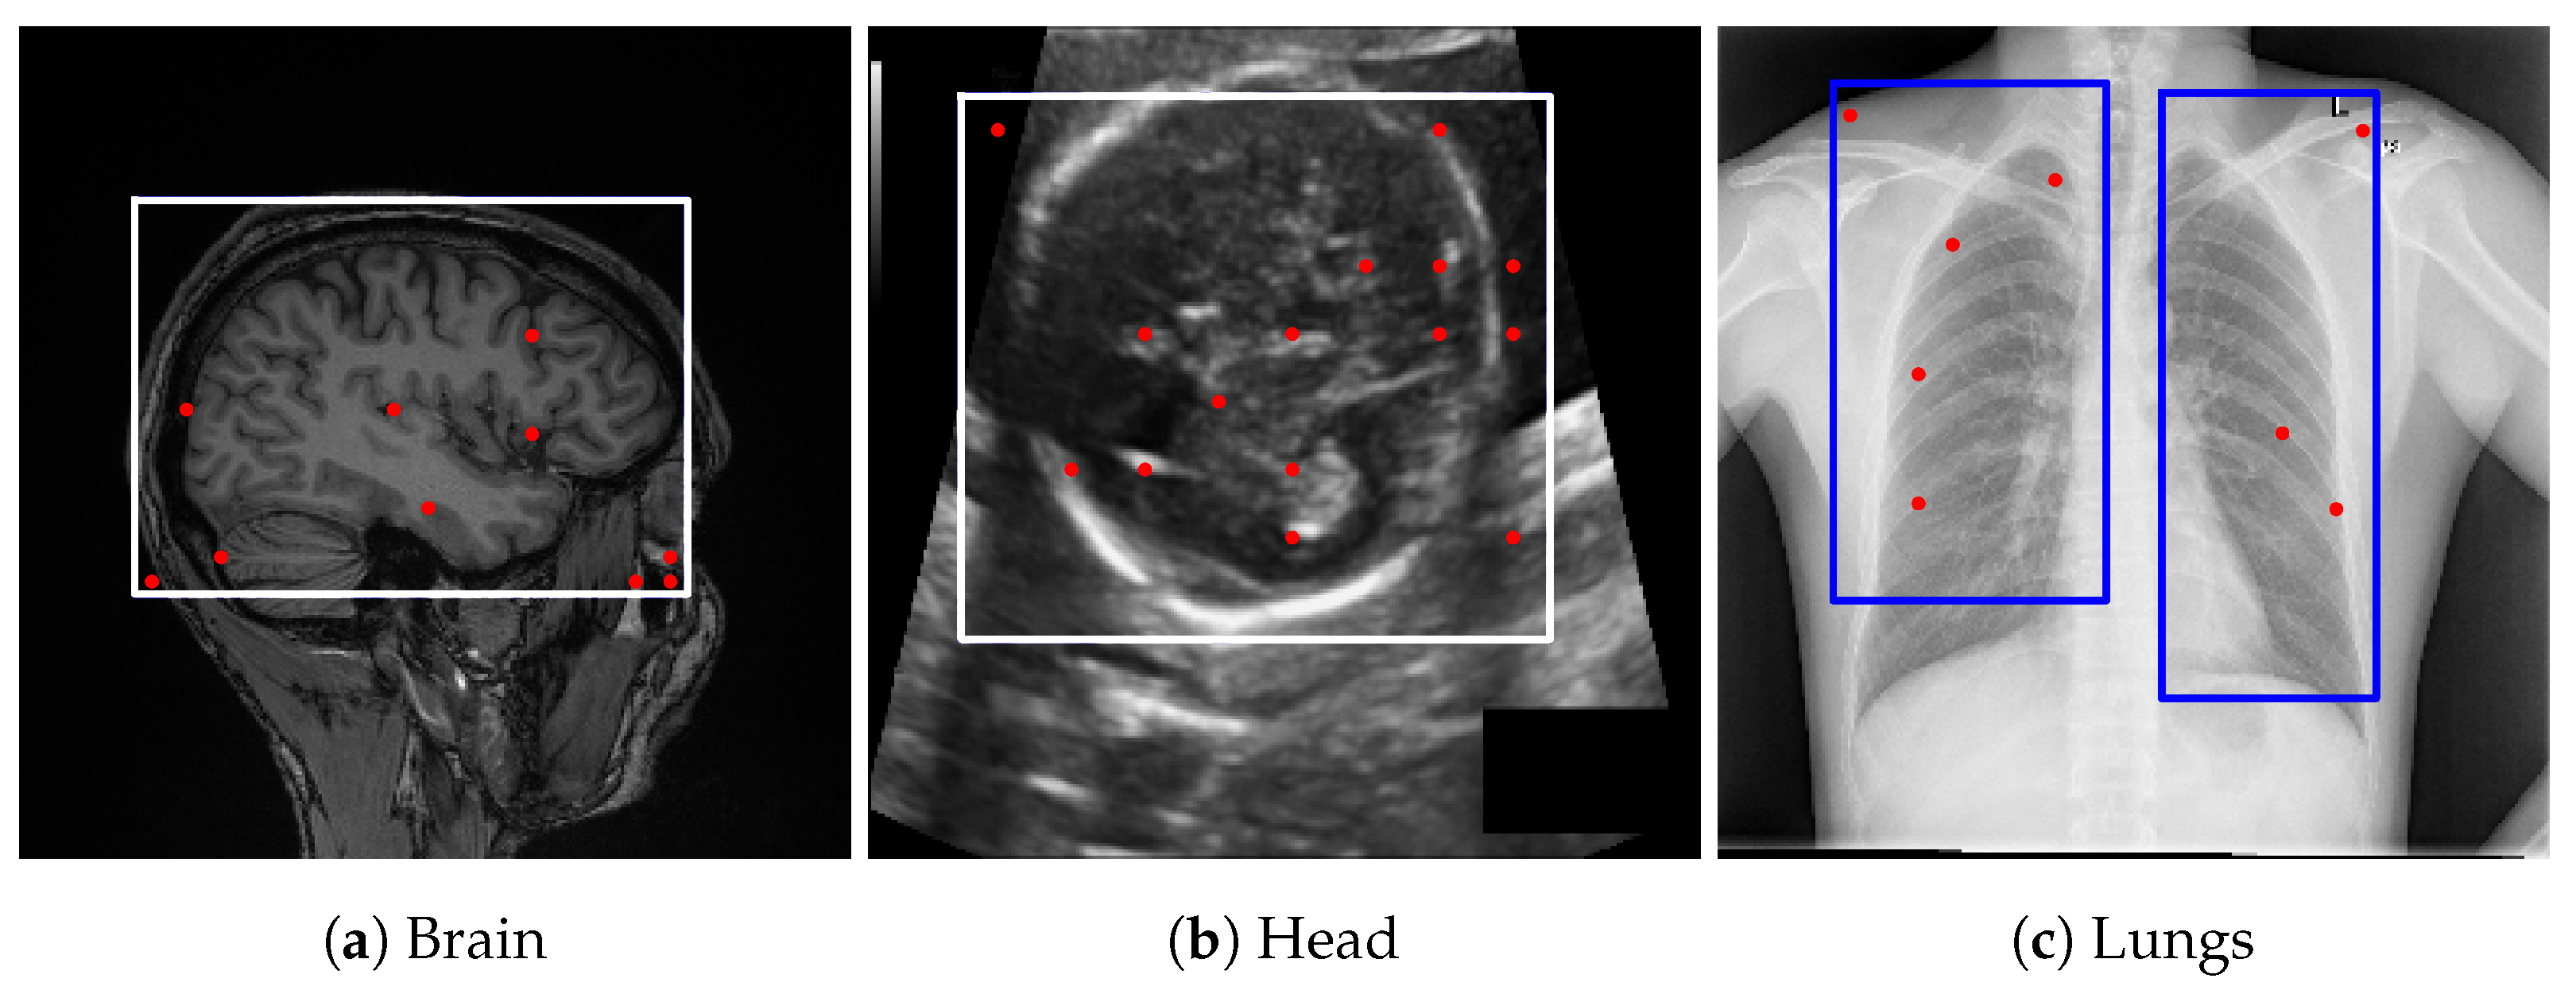

Figure 2. Examples of lung bounding box estimations generated by different models: LLaMA-4-Maverick-17B-128E, GPT-4o, and Gemini Pro 2.5. The blue rectangles indicate the bounding-box prompts, and the red dots represent the point prompts. Both are provided as inputs to the Segment Anything Model (SAM) to generate segmentation candidates.

Figure 3. Bounding box estimations by Gemini Pro 2.5 across different datasets. Blue rectangles and red dots indicate the prompts provided to SAM for generating segmentation candidates.

GPT-4o [13] demonstrated performance comparable to Gemini Pro 2.5 [9] in our internal evaluations; however, Gemini Pro 2.5, available from Google, was chosen for downstream experiments due to its consistent accuracy, stable API access, and available research funding for sustained API usage. It also outperformed LLaMA-based models, as shown in Figure 2. Model outputs were returned in JSON format and integrated directly into our segmentation pipeline. While the bounding box estimations generated by Gemini across multiple datasets were not sufficiently precise to serve as final segmentations, they consistently localized the region of interest. Despite occasional boundary inaccuracies, these estimations provided reliable spatial priors that effectively guided the SAM model towards more accurate segmentations, as illustrated in Figure 3.

4.5.4. Prompt Engineering and Choice of Large Vision-Language Models for Bounding Box Estimation

To derive reliable bounding box priors, we designed structured prompts that explicitly defined both the target anatomical structures and the spatial constraints of the bounding box. The final prompts used in our pipeline are provided in Appendix B. These prompts were tested across several LVLMs, including maverick-llama-4, GPT-4V, and Gemini Vision. While multiple models could generate bounding boxes, we selected Gemini Pro 2.5 for its consistent alignment with regions of interest and compatibility with available computational resources. In contrast, alternative models often produced loose or misaligned boxes, which degraded downstream segmentation accuracy. Representative bounding box results from different models with the same prompt are shown in Figure 2, underscoring the importance of prompt engineering and the sensitivity of the pipeline to LVLM choice.